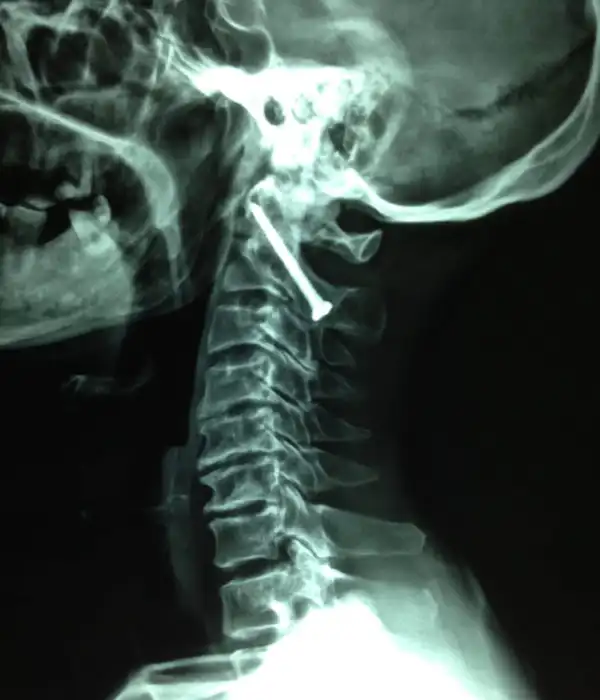

Occipital Cervical Spine

Instability in the atlanto-occipital joint results in hyper-mobility of the junction between the head and the neck which can cause severe pain or paralysis. It may result from rheumatoid arthritis or congenital defects that can accelerate degenerative arthropathy, resulting in spinal cord compression. At Kauvery Advanced Spine Centre, we use the latest developments in imaging, computer-assisted surgery, and instrumentation to provide safe surgery.

Conditions That Can Be Treated

- Chronic Cl – C2 instability

- Degenerative Cl – C2 joint

- Congenital problems

- Odontoid fracture

- Rheumatoid arthritis

- CT guided injections

C1-C2 instability Post OP X ray

C1-C2 fusion Post OP X ray